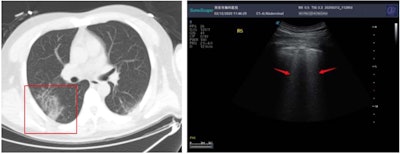

Above: A CT scan and ultrasound scan from one patient with COVID-19. Below: A CT scan and ultrasound scan from a second patient with COVID-19. All images published in SSRN and courtesy of Yi Huang and colleagues.During the early stages of COVID-19, patients tended to exhibit focal B-line patterns, followed by alveolar interstitial syndrome as the disease progressed. In patients who were critically ill, ultrasound scans showed A-line patterns in the convalescence. For patients with pulmonary fibrosis, the scans found pleural line thickening with uneven B-line patterns.

Similarly, the chest CT scan of one patient in Huang and colleague's study showed ground-glass opacity and air bronchogram sign under the pleura of one lung (Figure 1). The ultrasound scan of the same patient revealed an uneven pleural line and B-line patterns (Figure 2).